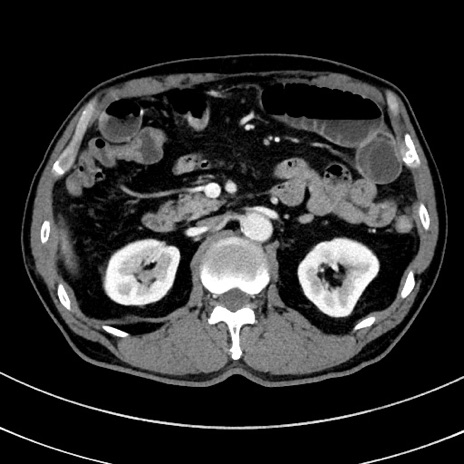

症例8(横断像)

【症例】 60歳代男性

【主訴】 黒色吐物

【現病歴】 4日前から嘔気自覚、2日前の朝食後にも嘔気あり、自分で手で嘔吐反射起こし嘔吐したところ血が混ざっていたため受診。

【既往歴】 5年前汎発性腹膜炎を伴う急性虫垂炎で手術、高血圧、前立腺肥大症、高脂血症

【身体所見】 腹部正中に手術癩痕あり 腹部平坦・軟圧痛なし膨満感あり

【データ】WBC 8400、CRP 4.54